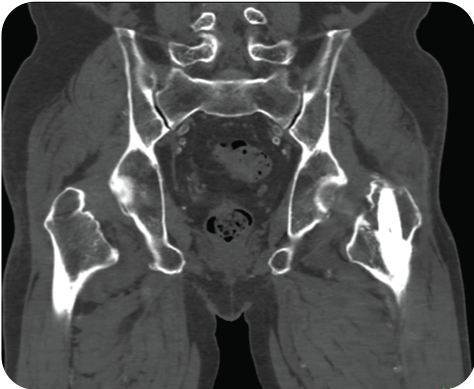

Incisive CT的O-MAR技术能消除金属伪影,能清晰显示移植物的位置及临近组织结构。

▲ 骨折术后、内固定器材清晰显示